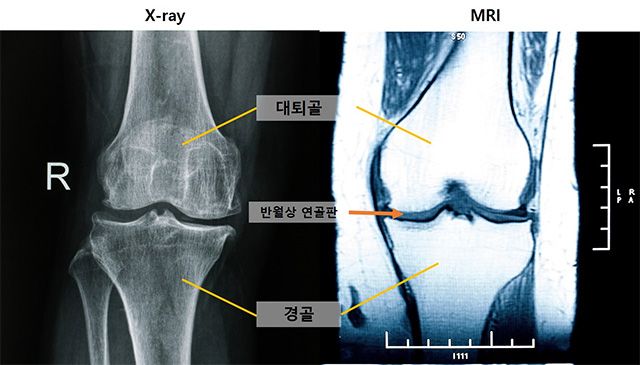

- ▲ 무릎 관절염 진행 단계에 따른 MRI 소견. 관절염 0기(빨간 선)에서도 ‘중앙 대퇴골 연골 손상’이 관찰돼, 이 손상이 무릎 관절염의 중요한 초기 증상으로 나타났다. /이미지 제공=서울대병원

분석 결과, 관절염 진행에서 가장 먼저 나타나는 변화는 ‘중앙 대퇴골 연골 손상’이었다. 이는 엑스레이상 정상으로 분류되는 관절염 0기(KL 0기)에서도 관찰돼, MRI가 조기 변화를 포착하는 중요한 도구임을 보여줬다.

연구팀은 ‘반월상 연골 탈출(extrusion)’이 무릎 관절염 진행 위험을 강하게 예측하는 지표라는 사실도 확인했다. 이는 단순한 추적 기간보다 무릎 내부의 구조적 변화가 질환 악화에 더 큰 영향을 미친다는 의미다.

MRI에서 먼저 발견된 변화는 시간이 지나면서 엑스레이에서도 확인됐다. 구체적으로는 경골 골극, 내측 관절강 협착, 대퇴골 골극 순으로 나타났으며, 모두 MRI에서 확인된 연골 손상과 밀접하게 연관돼 있었다.